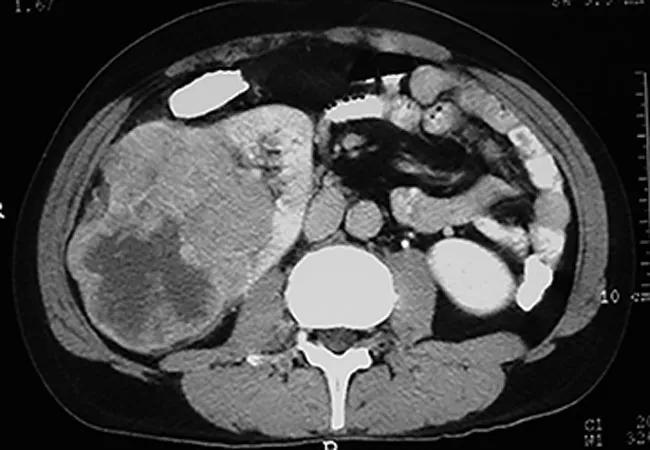

Certain carefully selected metastatic renal cell carcinoma (mRCC) patients who choose close monitoring rather than immediate systemic therapy can live for months or several years before cancer progression while avoiding the significant burdens of treatment, a Cleveland Clinic-led study has found.

Study participants underwent baseline and regular repeat CT scans and clinical assessments to determine change in tumor burden and time to progression. They also were periodically assessed for quality of life, anxiety and depression status changes. Overall survival, progression-free survival and best overall response after therapy (the latter for those participants who discontinued active surveillance and initiated treatment) were recorded.